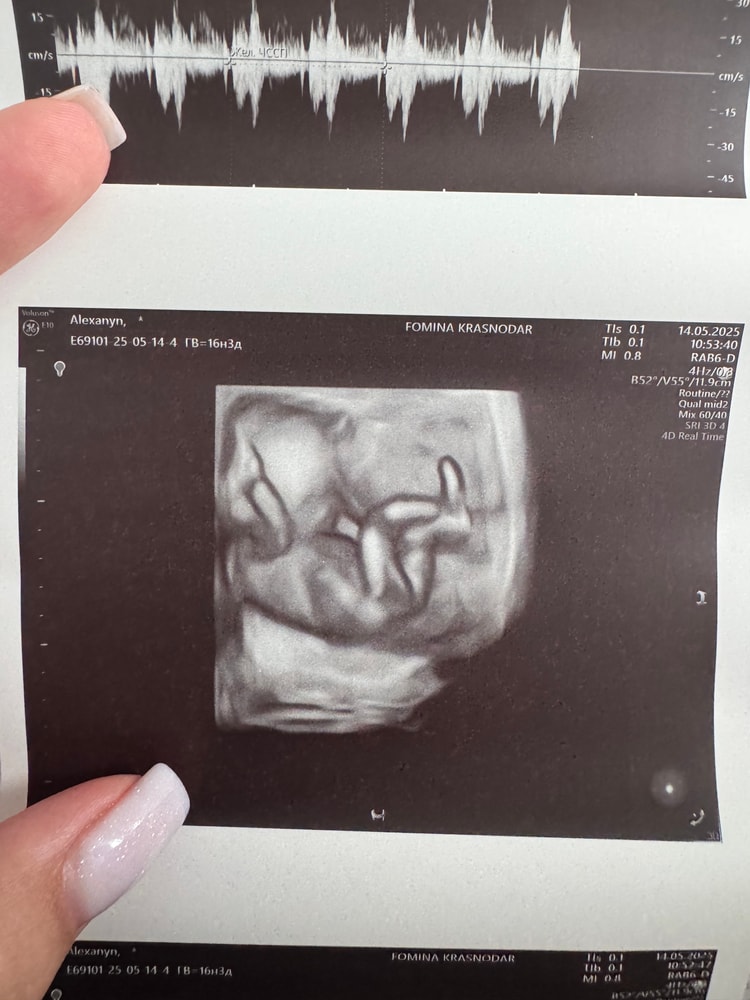

Помогите определить пол)

Пол малышаДевочки, на первом скрининге и потом в 16, 4 сказали что девочка, а сегодня была на цервикометрии и похоже у нас новые обстоятельства отросли)))) я переспросила еще не может ли это быть пуповина, врач сказала, что пуповина бы кровоток показывала, а тут нет… я уже настроилась на девочку)))))

Как и у вас. Очевидно все. Мальчик)